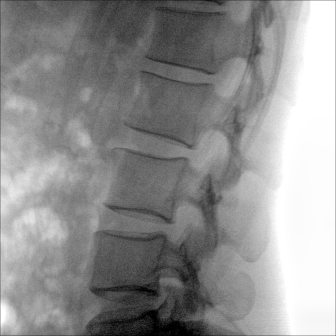

大尺寸動(dòng)態(tài)平板探測器,高DQE、低噪聲、圖像清晰。采用多分辨率圖像增強處理技術(shù),不同部位不同圖像處理算法,滿(mǎn)足客戶(hù)多樣化的需求。

采用智能變頻脈沖透視技術(shù),優(yōu)化圖像質(zhì)量的同時(shí)降低輻射劑量,呵護醫患健康